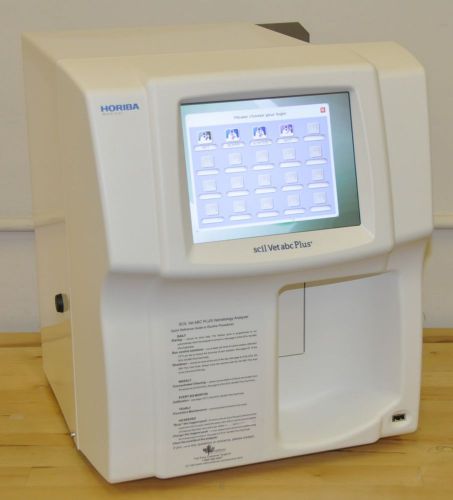

SCIL VET HORIBA VET ABC PLUS VETERINARY HEMATOLOGY BLOOD ANALYZER CBC